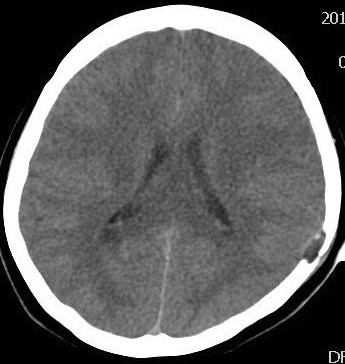

1.X线/CT:显示溶骨性破坏(边界清晰,局限性颅骨缺损,缺损边缘不规则呈“虫蚀样”改变,颅骨内外板受破坏,在病变组织内可见条索小骨影,病变周围可见软组织块影征象)。

2.MRI:评估软组织受累范围。